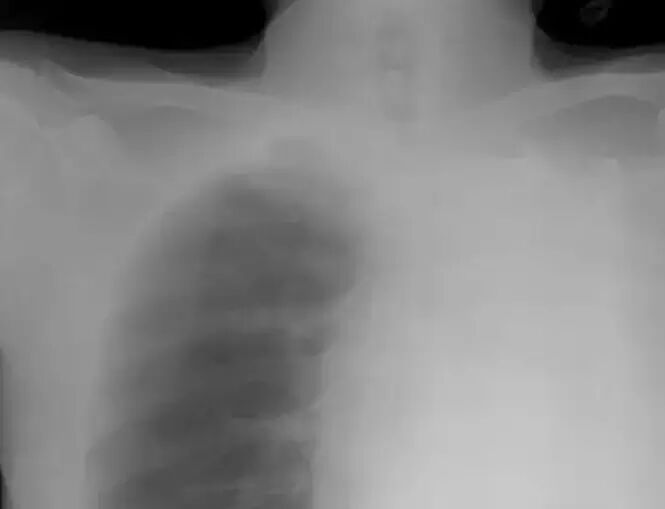

常人的胸片都有左右对称的两个肺,但小雷的片子只能看到右侧的一个肺,左肺的位置上一片空白。左肺怎么不见了呢?

看到这个片子,小雷也吓了一跳。过去30多年中,他没有感到任何不适,难道他是天生的“单肺人”?